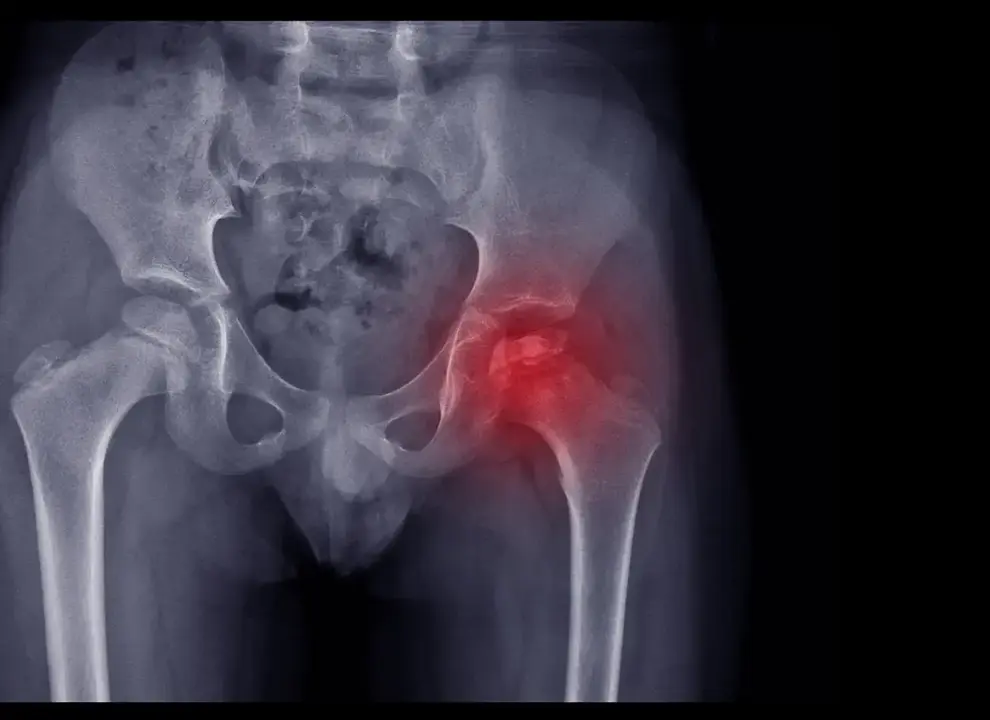

Las familias reclaman que el 17 de enero se dedique a esta enfermedad rara que afecta a la cadera de los niños

La enfermedad de Legg-Calvé-Perthes es una necrosis avascular de la cabeza del fémur que aparece en niños de entre 3 y 12 años. El principal obstáculo, según las familias, es el desconocimiento. Tal y como advierte la presidenta de ASFAPE y portavoz de la campaña, Elena Fernández de Mendiola, el Perthes se confunde con frecuencia con molestias leves:

El Perthes no tiene una causa conocida. La interrupción del riego sanguíneo provoca la muerte del hueso, que el organismo acaba regenerando con el tiempo. El reto médico es que ese nuevo hueso crezca con la forma esférica adecuada para garantizar una buena funcionalidad de la cadera.